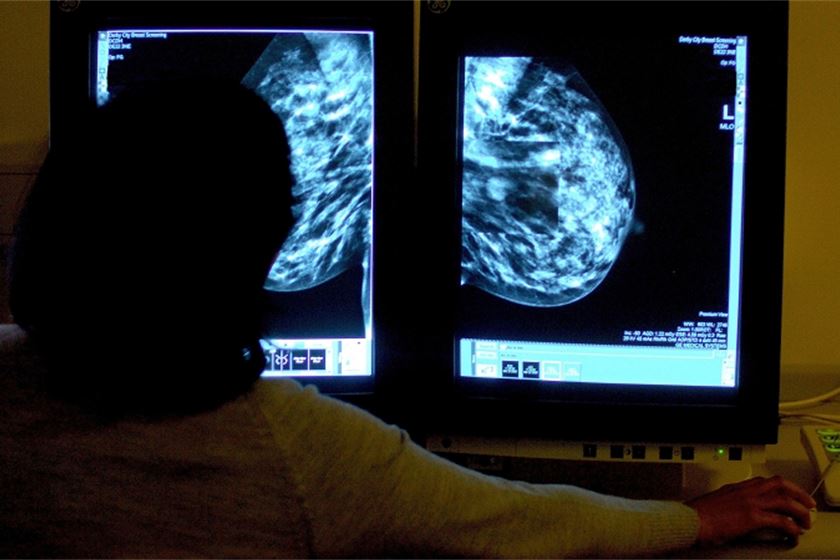

“One in two of us are going to get cancer in our lifetime. Although that means a lot of cases of cancer, it's essentially a different disease in us all, and we're increasingly understanding that at a molecular level,” Collins says. “The real challenge for medicine now is how do I treat the patient sitting in front of me. It's not about a trial, it's not about understanding the textbooks, the statistics – it's how do I find the other dozen patients who are like this person sitting in front of me with breast cancer, with the same molecular abnormalities, the same risk factors, the same treatment profile.”